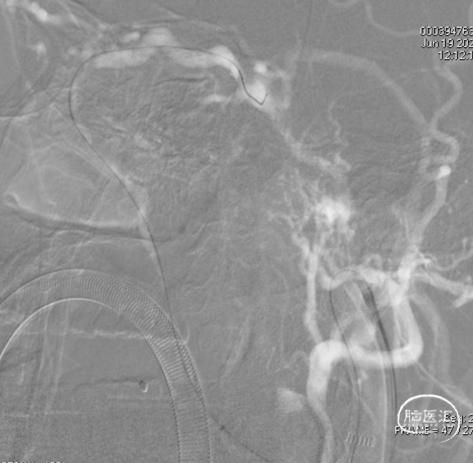

左侧咽升供血的HCDAVF,逆流至海绵窦,经眼上静脉-面静脉引流。

1、瘘口经同侧咽升动脉供血,动脉入路栓塞可能因栓塞过程中胶的返流导致后组颅神经麻痹,或通过危险吻合进入颈内系统;该瘘口主要返流海绵窦,经眼上静脉-面静脉引流,可经静脉入路使用Onyx胶栓塞,术中为避免Onyx的过度弥散,考虑结合弹簧圈栓塞。

Echelon微导管超选面静脉,后通过眼上静脉超选至海绵窦,进一步超选至瘘口,微导管造影确认在位。